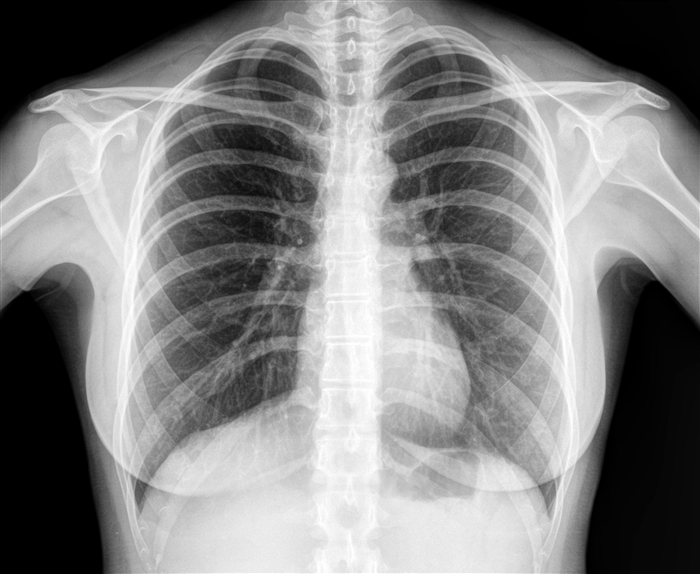

胸のレントゲンで心臓が大きいといわれた

胸のレントゲンだけでは必ずしも

心臓の正しい大きさがわからない

こともありますが、

実際に心臓が大きくなっている兆候が

レントゲンにあらわれることがあります。

心臓が大きくなる場合、

心臓の動きが悪くなっていたり、

心筋症(しんきんしょう)

のような病気が原因の場合があります。

心エコーでは、こうした病気の特徴を

調べることができます。